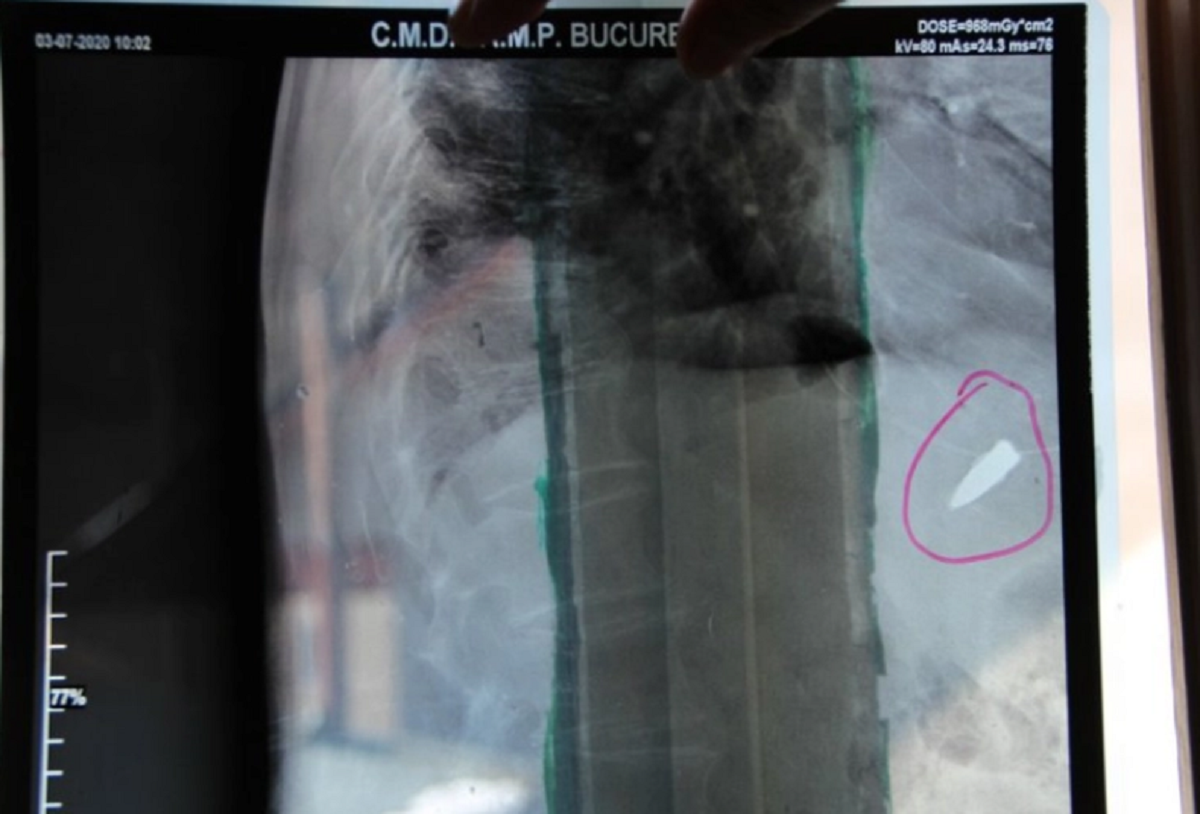

El este românul care trăiește de 80 de ani cu un glonț lângă inimă. Povestea care a făcut înconjurul lumii